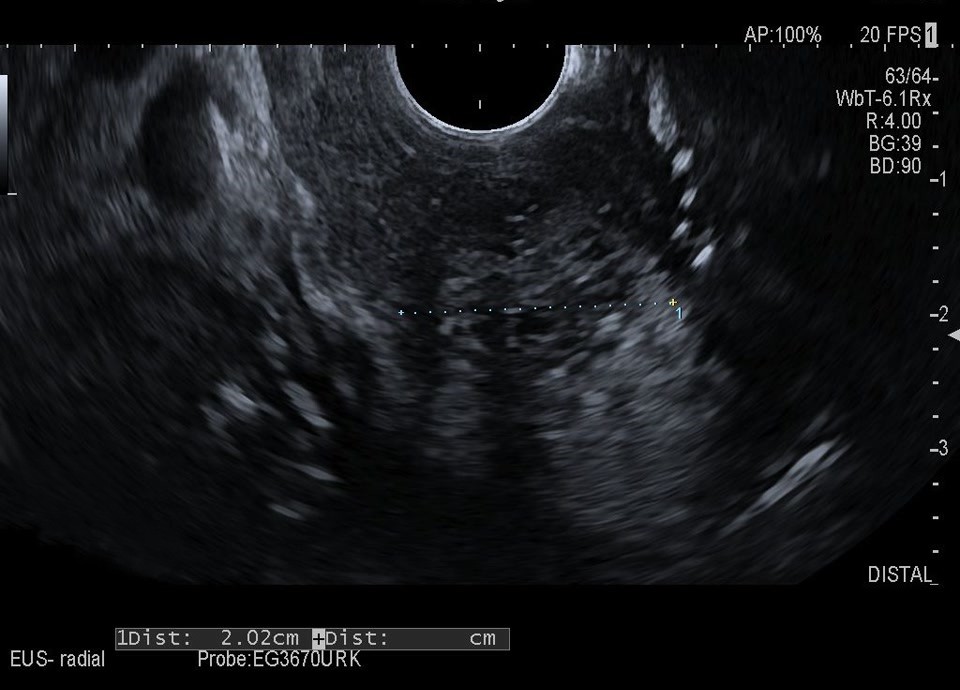

Case

60-year-old female patient with incidental finding of serous cystadenoma one year ago. Current follow-up examination reveals small cystic mass (honeycomb pattern visible on EUS) of constant size in the head of the pancreas/uncinate process. In the transcutaneous B-scan, central echogenic portion (central scar), hypervascularized on color Doppler sonography.